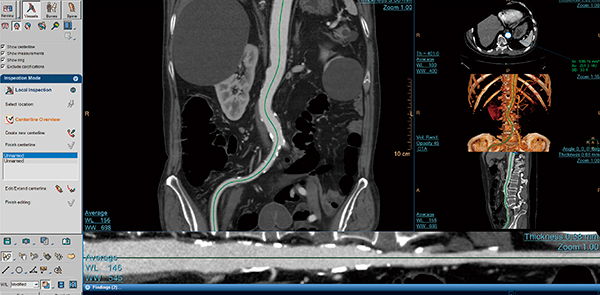

●CT用アプリケーション “CT Acute Multi Functional レビュー”

CT Acute Multi Functionalレビューは,救急CTにおいて生命を脅かす状態の検出だけでなく,病院内の関係者への迅速な情報の提供を目的とした統合型アプリケーションである。基本的な画像表示と血管観察に特化したVesselモード,骨折に対応したBoneモード,椎体観察に特化したSpineモードがあり,目的に応じた画像観察が迅速に行えるようになっている。Vesselモードでは,画像上の血管を1クリックすると,周辺情報とともに短軸像が観察できる。また,2点間を指定することにより,血管をストレッチ観察することができる(図4)。血管解析ソフトウエアのように骨除去のプロセスを必要としないため,短時間で腹部大動脈瘤の測定や石灰化付着,周辺情報など目的の情報を得ることができる。Boneモードでは,開放骨折のような状態でも骨の破片をセグメンテーションしてパーツ化することができるため,三次元での複雑な角度調整を伴った接骨シミュレーションが可能となる。Spineモードでは,頸椎から腰椎に至るまで,全脊椎の自動MPR作成と椎間板に沿ったラベル付きアキシャル画像を得ることができる。なお,自動化されたMPR作成機能では,対話形式での細かな修正も可能である。

図4 CT Acute Multi FunctionalレビューVesselモード